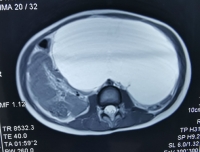

12月26日,儿童心血管科通过多学科协作完成了一例腹腔巨大淋巴管畸形的微创治疗。该5岁患儿腹腔包块巨大,压迫腹腔及腹膜后器官,之前辗转两家医院均未得到治疗。考虑到患儿年龄小,开腹治疗创伤大,经儿童心血管科与小儿外科、超声科讨论后,决定联合进行腹腔置管引流及介入硬化术。术中患儿在超声引导下顺利完成腹腔穿刺置管,引流出1000ml囊液,并在DSA...